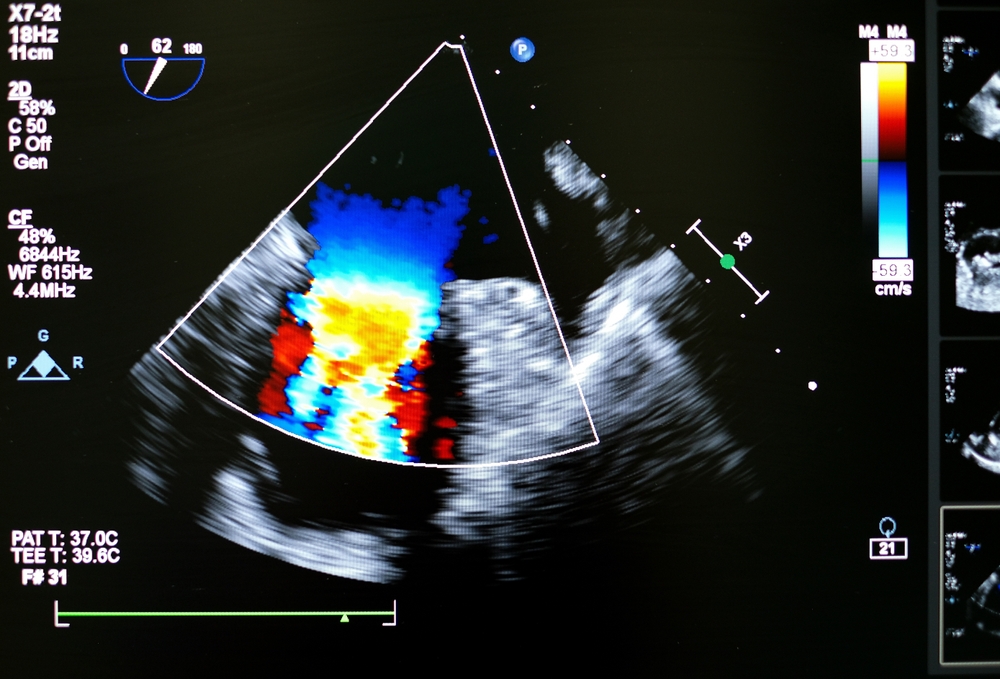

- Nowoczesny aparat USG – wysokiej klasy sprzęt pozwala na precyzyjną ocenę struktur serca i przepływów krwi.

- rozpoznać i monitorować wady zastawek,